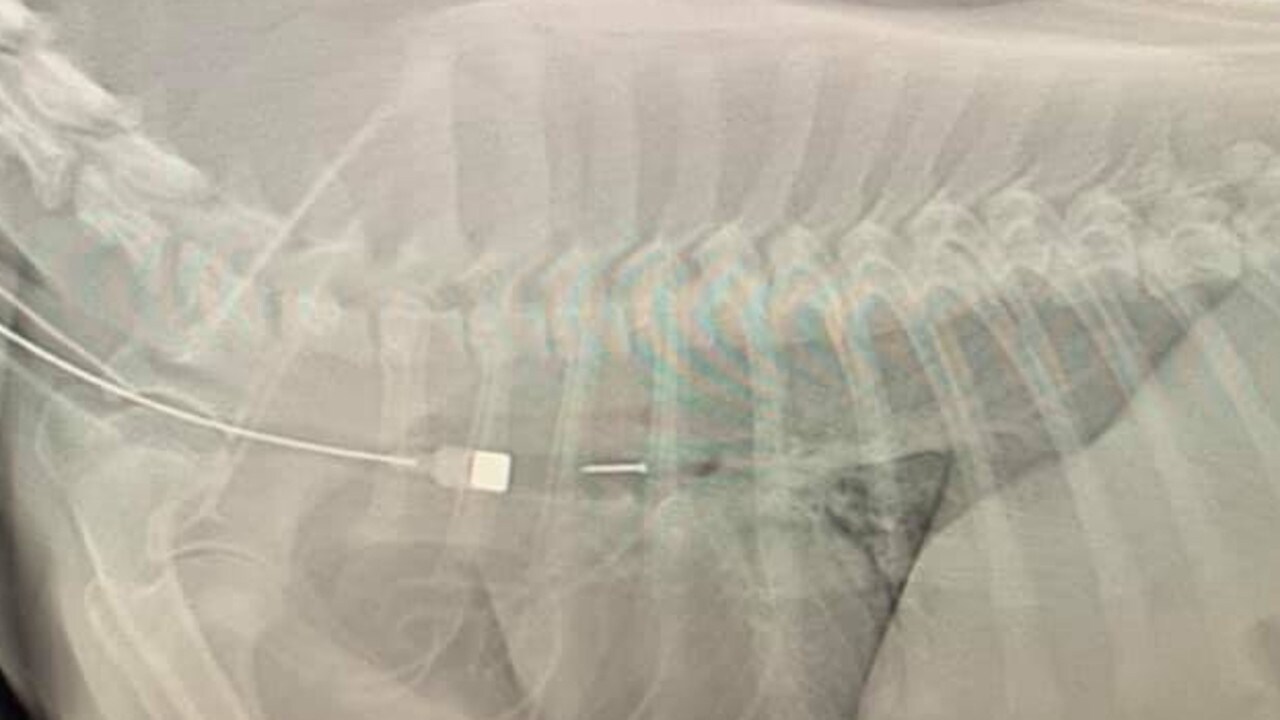

From www.itv.com

Vet rescues dog that swallows fish hook left on Devon beach ITV News Dog Swallowed A Thumb Tack One thing new research makes clear. The signs that your dog may have swallowed a thumbtack can vary. If your dog has swallowed a toothpick, it is important to take immediate action. If your dog has swallowed something sharp, such as a bone fragment or needle, do not attempt to induce vomiting. Keep reading to know what our vets recommend. Dog Swallowed A Thumb Tack.